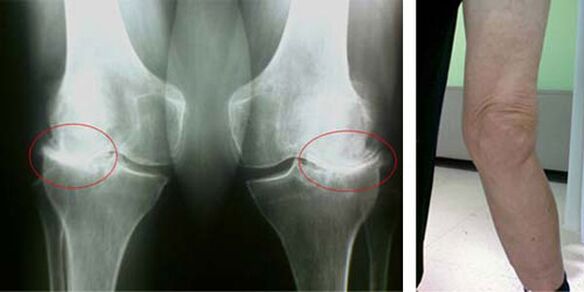

In a healthy knee joint, cartilage is a kind of lining that doesn't allow the bones to touch each other, thereby eliminating the possibility of damage while walking. Diseased cartilage cannot cope with this function, so during movement, signs of stiffness appear in the joint, accompanied by pain. This condition becomes permanent due to internal pathological changes, when the thinning of the cartilage tissue leads to the thickening of the bone and creates the conditions for the appearance of bone spurs - osteophytes, which cause acute pain.

The initial stages of the occurrence of such a pathology as osteoarthritis of the knee joint do not manifest themselves visually in any way. However, after some time, the patient notices signs of knee deformity, as well as a characteristic curvature along the axis of the lower leg (directed inward). There is also a crunch when you have to bend your leg.

The presence of pain, limited movement of the knee causes a person to see a doctor and undergo an examination. To do this, he must pass tests and take an x-ray of the diseased joint. If these measures are not enough to confirm osteoarthritis of the knee joint, MRI is done. Based on the collected data, the doctor chooses the best methods of treatment.